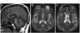

Binswanger's disease, also known as subcortical leukoencephalopathy and subcortical arteriosclerotic encephalopathy (SAE), is a form of small vessel vascular dementia caused by damage to the white brain matter. White matter atrophy can be caused by many circumstances including chronic hypertension as well as old age. [Source: Wikipedia ]